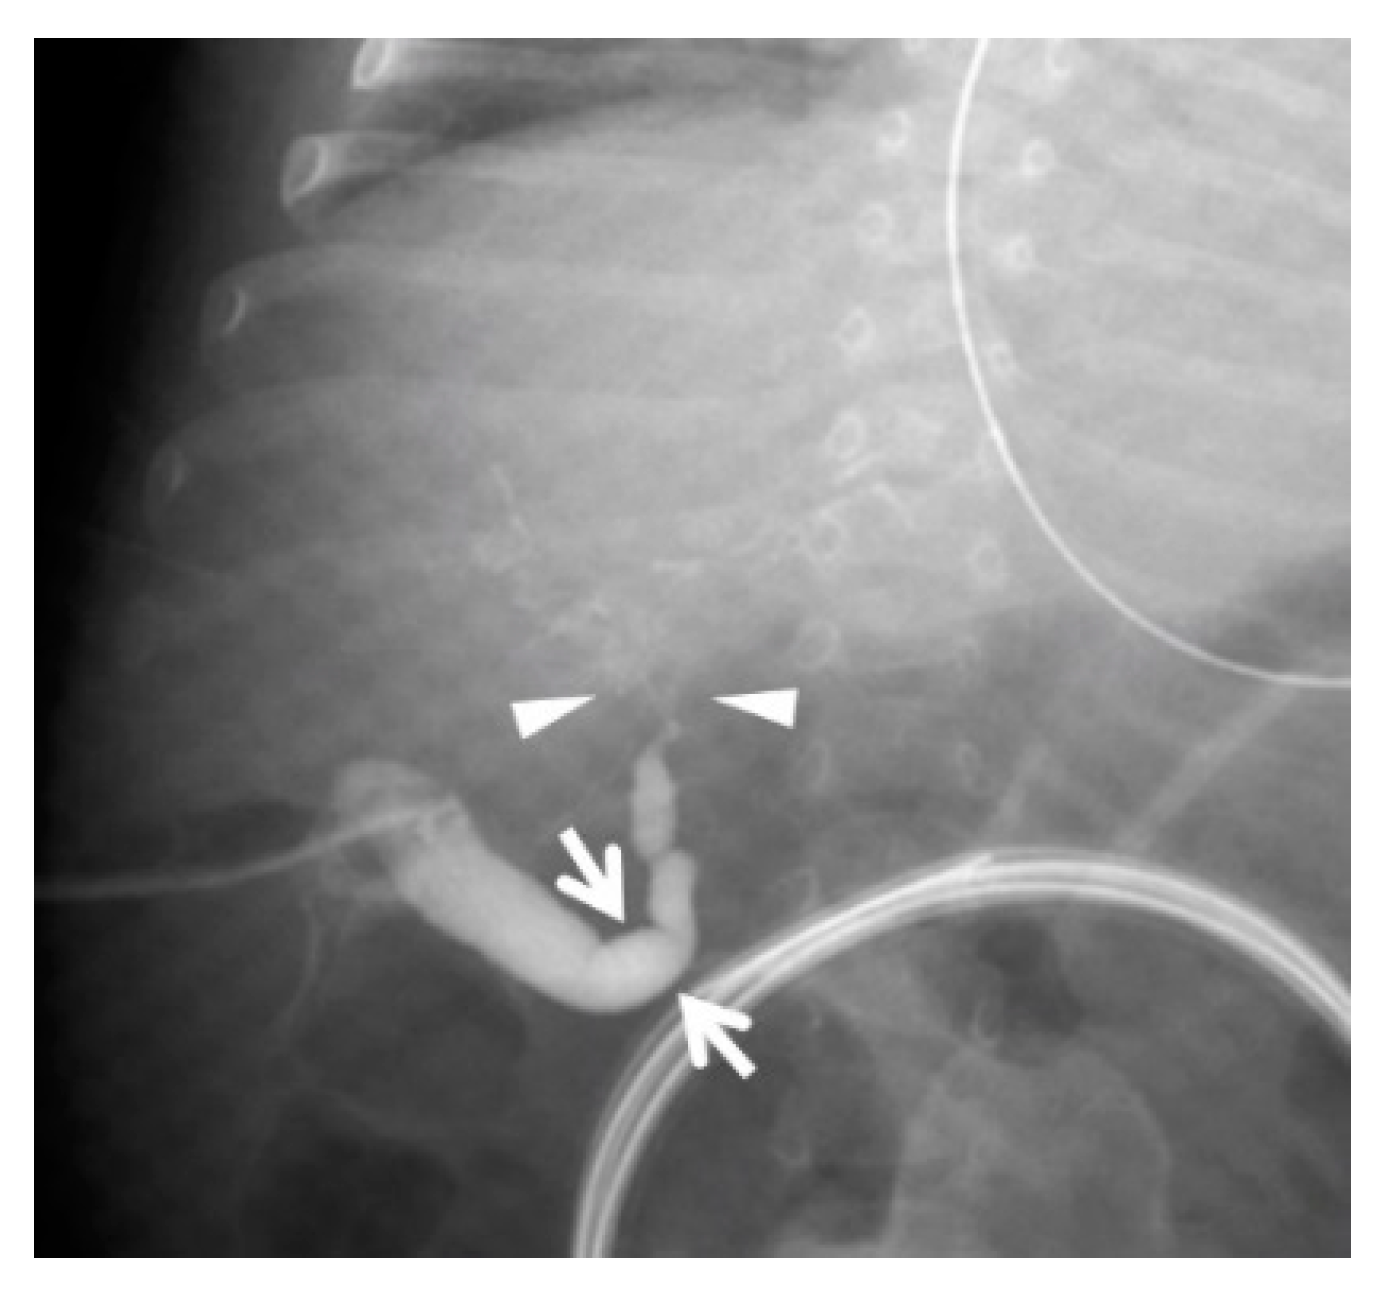

2.2. Case 2: 67-Day-Old Girl